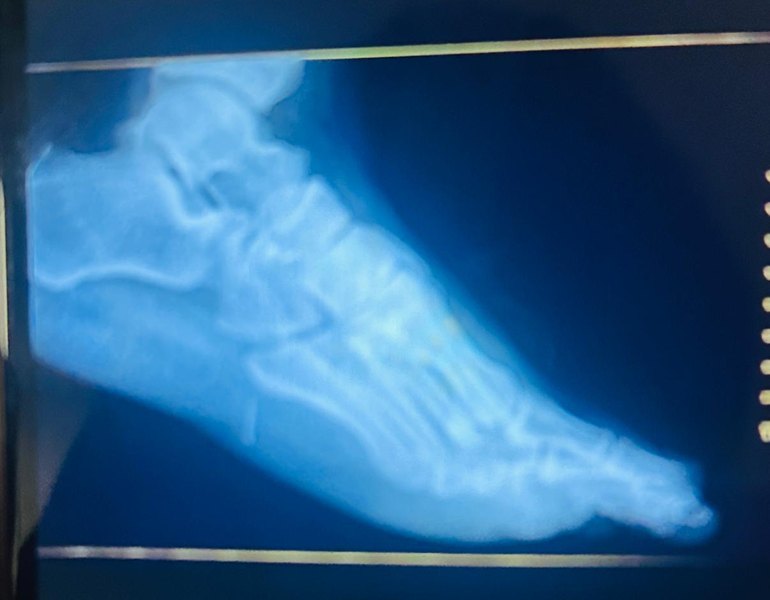

Inicialmente, a vítima foi levada para uma Unidade de Pronto Atendimento (UPA), onde os profissionais não conseguiram retirar o ferrão devido à profundidade do ferimento. Diante da complexidade do caso, ele foi transferido para o HRPI, onde passou por procedimento cirúrgico para remoção do objeto.

A cirurgia foi conduzida pelo cirurgião Rafael Pinheiro, que confirmou o sucesso do procedimento. Segundo ele, o ferrão foi retirado em fragmentos, sem deixar resíduos no local. O paciente recebeu alta médica com orientações de repouso e uso de medicação adequada para recuperação.